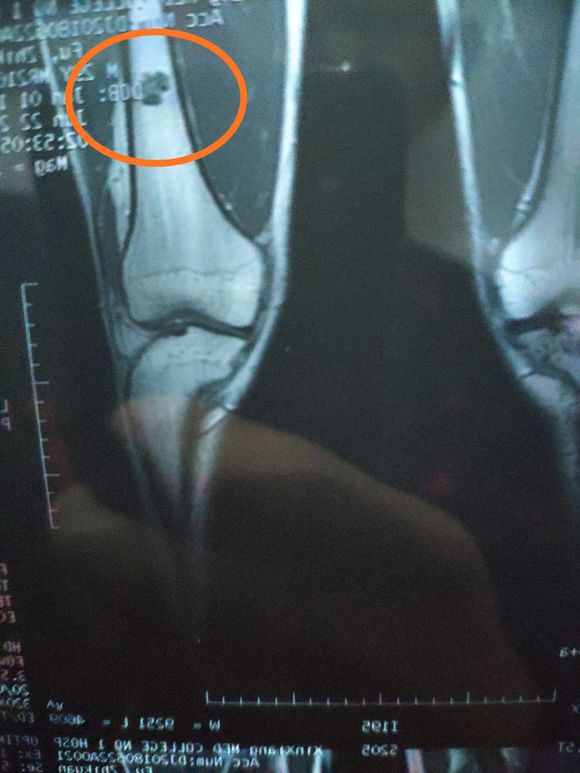

身心俱疲斗争 02019-02-22 患者家属女儿14岁,明天做截肢手术。医生让从髋关节处截,想保留个七八公分。问问大神们髋关节以下留七八公分能用常规的假肢吗? ...